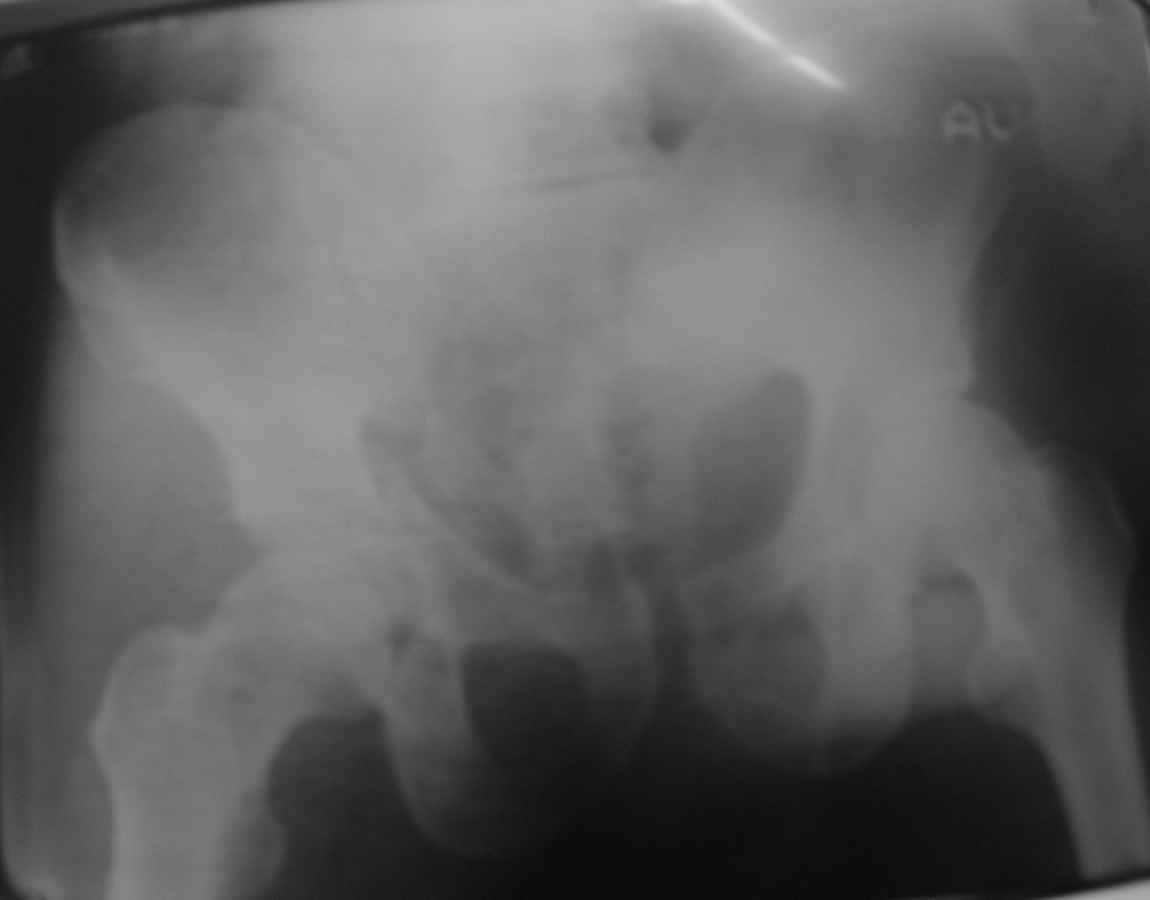

Уважаемые коллеги! Пациент 50 лет с переломом костей таза. Ваши рекомендации по лечению.

Имя     : 1.jpg